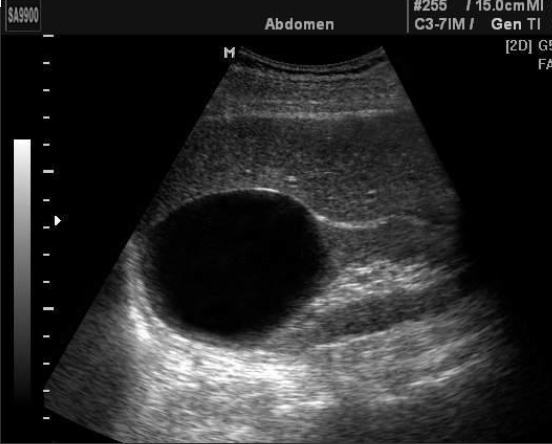

Simple Renal Cyst → common lesion of kidney, fluid-filled sac (benign, Bozniak 1)

clinical hx: incidence increases with age (50+), uncommon in children

s/sx: asymptomatic

2D US: anechoic, well-defined smooth, thin wall, round or ovoid, posterior enhancement

color doppler: avascular

DDX: complex cyst